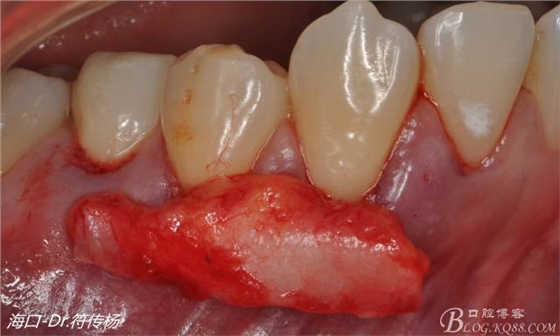

接著從腭部上皮下取出結(jié)締組織

確定取出結(jié)締組織長(zhǎng)度是否適當(dāng)